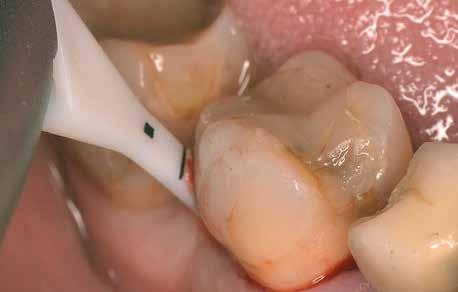

A cikk szerzőjének rendelőjében végzett kezelések során egy AIR-FLOW Master Piezon homokfújó készüléket (EMS; 6. ábra) és 0,3% klórhexidint tartalmazó erythritol port (AIR-FLOW PLUS powder, EMS; 14 μm-es átlagos szemcseméret) használnak a subgingiválisan elvégzett homokfújás során. A beavatkozás elvégzéséhez egy speciális thermoplasztikus elasztomerből készült, egyszer használatos csőrt alkalmaznak (7. ábra)

6. ábra: AIR-FLOW Master Piezon készülékkel végzett subgingivális homokfújás. 7. ábra: A beavatkozás során egy speciális termoplasztikus elasztomerből készített, egyszer használatos végződést alkalmazunk. 8. ábra: A készülékhez tartozó ultrahangos depurátor segítségével folytatjuk a kezelést.

dő nyílásból lép ki, és a fogak felszínének mechanikus módszerekkel történő tisztításával egyidejűleg, 5 má sodpercen keresztül a parodontális tasakot is átöblíti. Miután a AIR-FLOW Master Piezon készülékkel törté nő homokfújást befejeztük, megkezdjük az ugyaneh hez a készülékhez tartozó, ultrahangos depurátorral történő kezelést (8. ábra). A fent említett beavatkozá sokat általában helyi érzéstelenítés alkalmazása nélkül végezzük el.